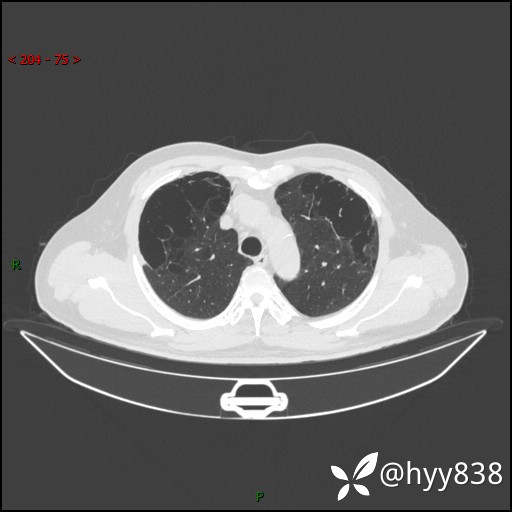

一周前胸部CT